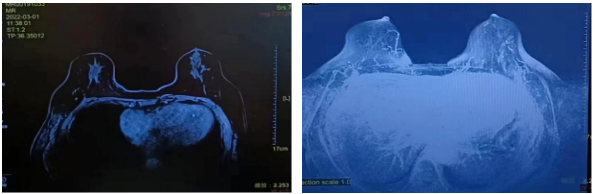

▌2022年3月1日新辅助第3疗程化疗后评价

肿块:无(原左乳内侧肿块,大小2.2cm*1.4cm)。

非肿块强化:无(原右乳内上及内侧肿物旁条片状影)。

同侧腋窝淋巴结:无,(原1枚肿大,大小约2.1cm*2.2cm,结构异常)

2022年3月01日

▌2022年5月12日新辅助第六疗程化疗后评价

肿块:无(原左乳内侧肿块,大小2.2cm*1.4cm)

非肿块强化:无(原右乳内上及内侧肿物旁条片状影)

2022年5月9日